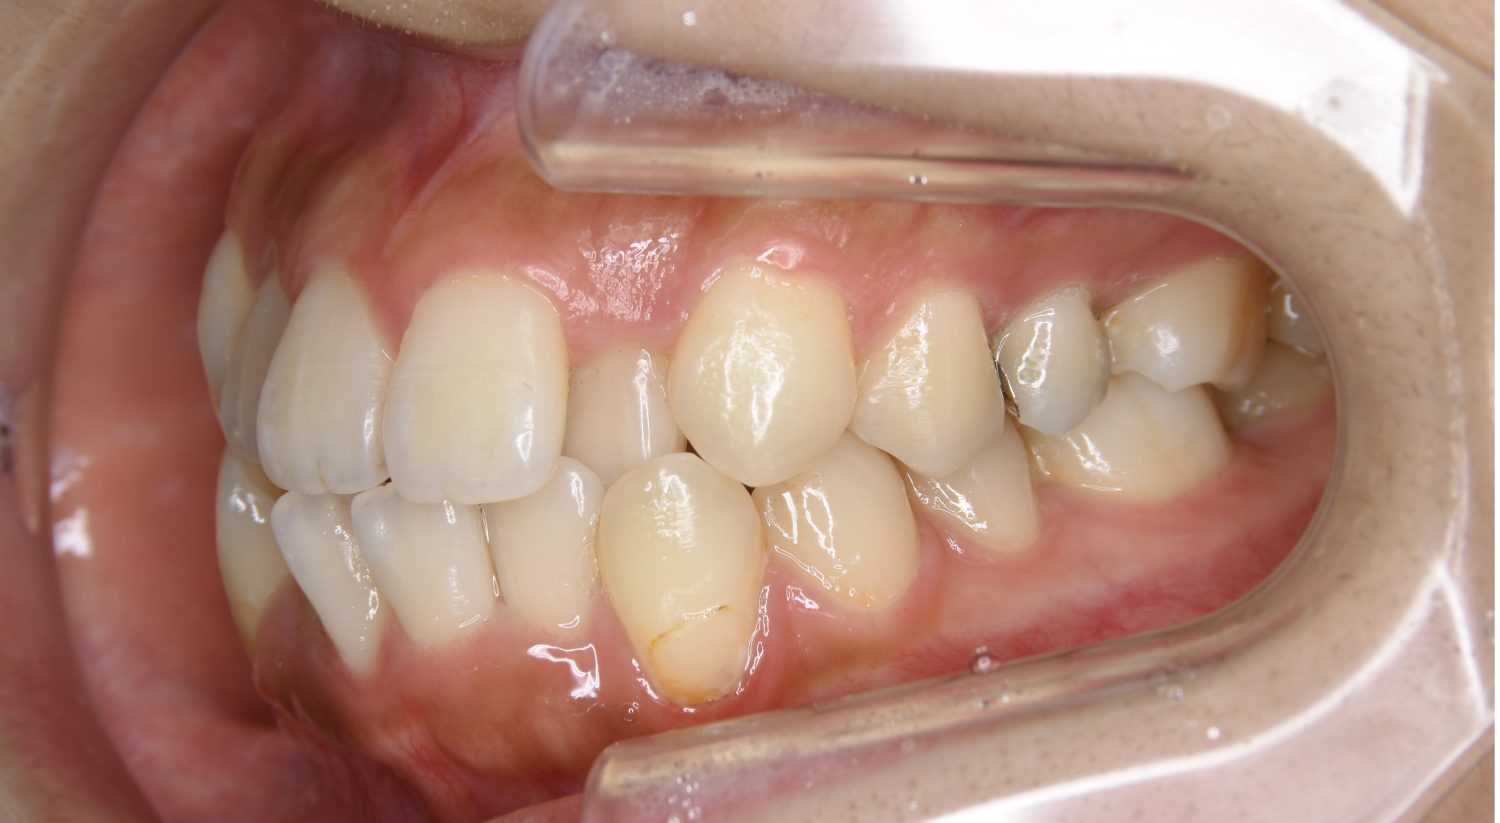

叢生の症例紹介②

Before

主訴

歯の凸凹を治したい。

治療内容

アライナー(インビザライン)にて非抜歯で治療を行いました。

上下前歯部に叢生(凸凹)が認められる状態でした。歯列の遠心移動を行うことで機能面および審美面が改善されました。